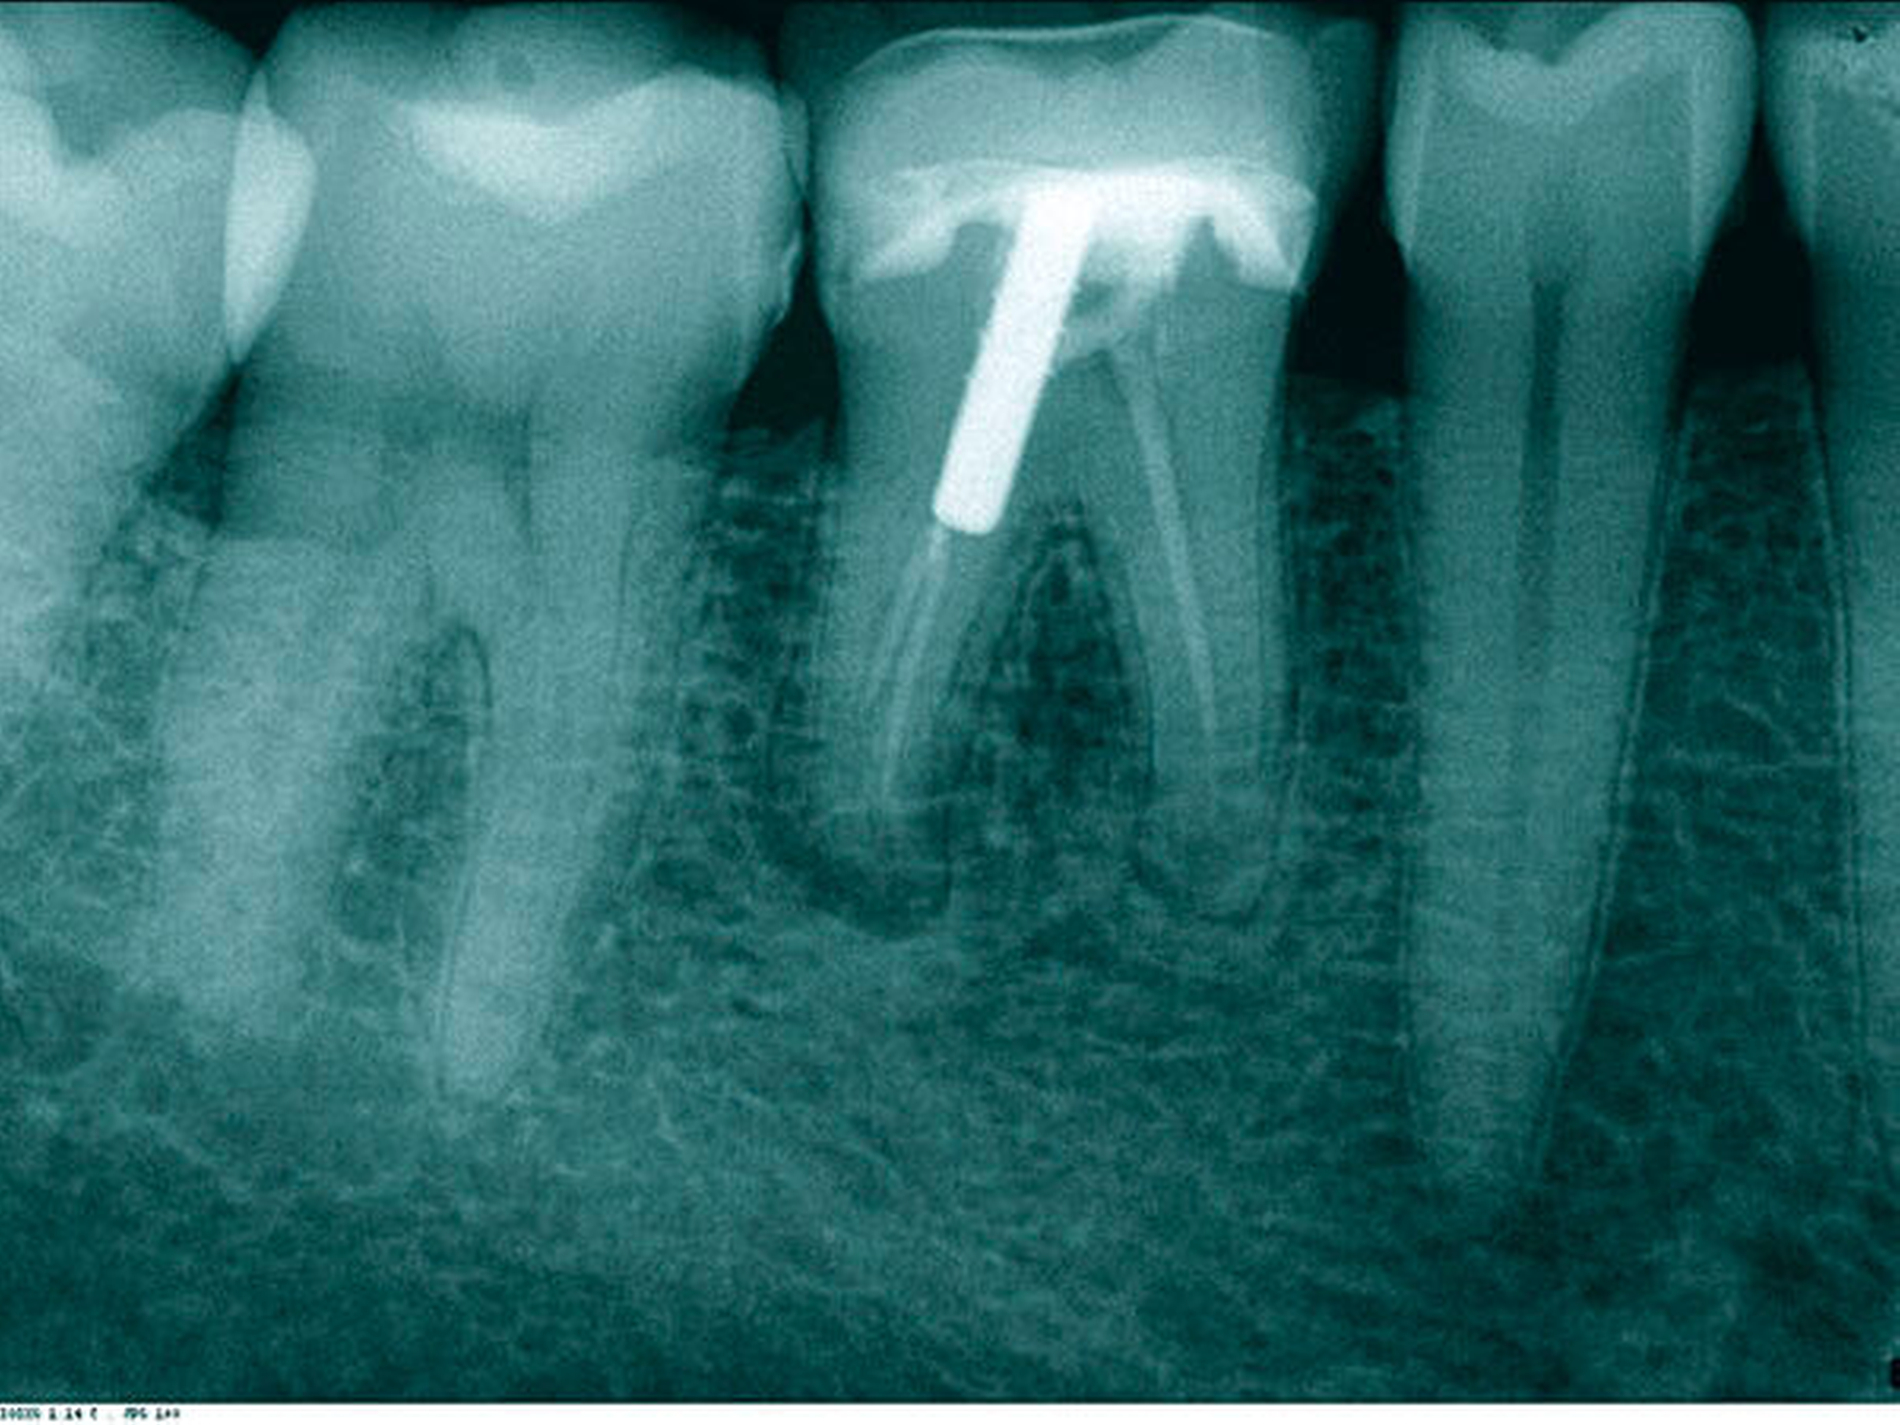

Ein 52-jähriger Patient wurde für die Revision des Zahnes 46 überwiesen. Zum Zeitpunkt der Überweisung klagte der Patient über diffuse, sporadisch auftretende Schmerzen und eine leichte Empfindlichkeit beim Aufbeißen und auf Perkussion. Der Zahn war vor 15 Jahren reseziert worden, die Krone war sieben Jahre alt. Das präoperativ angefertigte Röntgenbild zeigte eine insuffiziente Wurzelkanalfüllung mit apikaler Aufhellung an beiden resezierten Wurzelspitzen. Die mesiale Wurzel wies nur einen abgefüllten Kanal auf, in der distalen Wurzel war ein Wurzelstift aus Metall zur Verankerung eingebracht (Abbildung 1).

In der ersten Therapiesitzung erfolgte – nach Isolierung mit Kofferdam – die Trepanation des Zahnes und die Stiftentfernung mit Ultraschallinstrumenten. Im Anschluss wurden die drei gefüllten Kanäle revidiert, der vierte, nicht abgefüllte, mesiobukkale Kanal dargestellt und präpariert. Die elektronische Längenmessung ergab 14,5 mm für den mesiobukkalen Kanal, 17,0 mm für den mesiolingualen, 15 mm für den distobukkalen und 16 mm für den distolingualen. Aufgrund der großen initialen Kanaldurchmesser und der guten Einsicht bis ins periapikale Gewebe (Abbildung 2) wurde auf eine Längenmessaufnahme verzichtet. Die Desinfektion erfolgte mit Natriumhypochlorid (NaOCl) 5 Prozent und EDTA 17 Prozent, sowie Schallaktivierung mittels EDDY-Spitzen (VDW, München). Das Wurzelkanalsystems wurde manuell mit K-Feilen bis IS0 70 präpariert. Es folgte eine medikamentöse Einlage mit AH Temp (DentsplySirona, Bensheim). Danach wurde eine Aufnahme zur Kontrolle der vollständigen Guttapercha-Entfernung und der suffizienten Einbringtiefe des Kalziumhydroxids angefertigt (Abbildung 3).